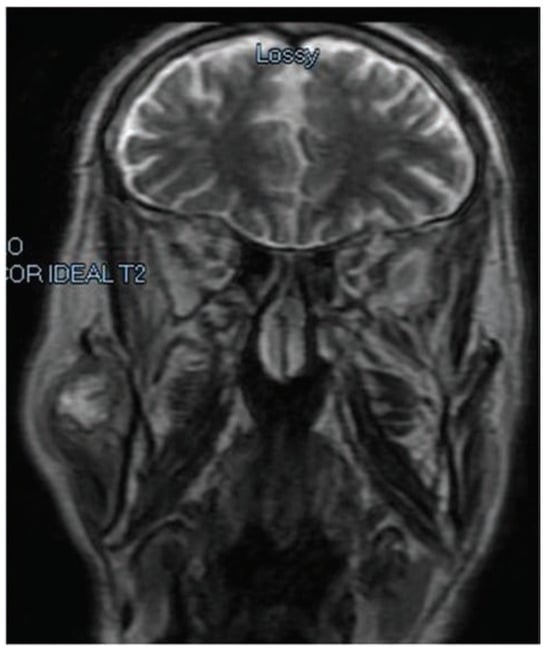

Ultrasound revealed a mass, around 3 cm diameter, in contact laterally with the parotid gland and medially with the masseter muscle. Magnetic resonance imaging (MRI) revealed a nodular lesion with substantially lobulated margins, including small hypointense foci in T2 with calcific meaning in the right preauricular region between the parotid gland and the muscle masseter. The lesion appears extrinsic to the parotid and shows no signs of infiltration of the nearby structures (Figure 2 and Figure 3). Two fine-needle aspirations were performed but did not result in a diagnosis.

Figure 3. Magnetic resonance imaging coronal view of the lesion.